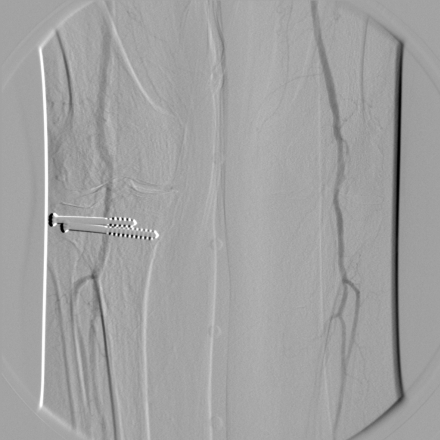

The split mask mode allows you to apply different pixel shifts for the left and right parts of the image. This can be helpful with lower-limb fluoroscopy image in which the limbs move in different directions, and there is no means of correcting the mask with a single, global shift.

Uncorrected mask |

Mask corrected for the right limb |

Mask corrected for the left limb |

To enable the split mask mode, select the  button or use the Ctrl + Alt + / shortcut.

You can subsequently correct the masks on both sides of the image using the manual or automatic pixel-shift tools.